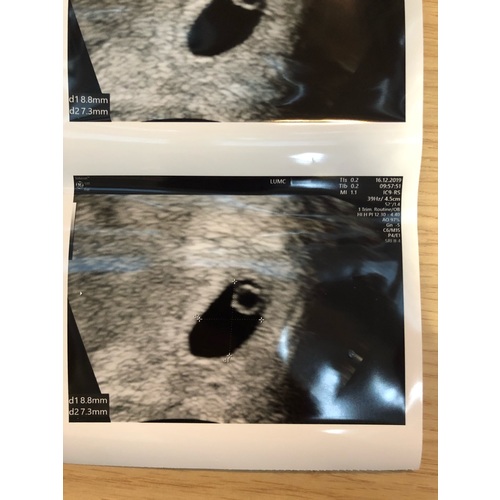

Deze echo was met ongeveer 6 weken, dooier zakje zichtbaar en een kloppend hartje (inwendige echo).

Ik loop bij de herhaalde miskraampoli en had met 5 weken al de eerste echo. Ik mag wekelijks komen als ik dat wil. Mij geeft het houvast, tuurlijk het kan misgaan, dat kan altijd, maar de kans dat het misgaat als alles op schema loopt en je een kloppend hartje hebt is gelukkig kleiner dan dat het wel goed gaat.